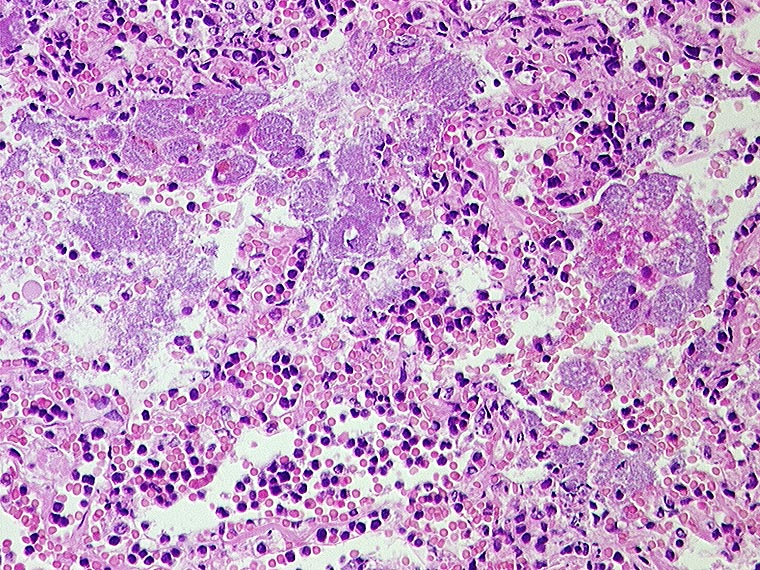

Areaktive Pneumonie

Entzündung infektiös

Lunge

Morphologie

Pathologischer Befund